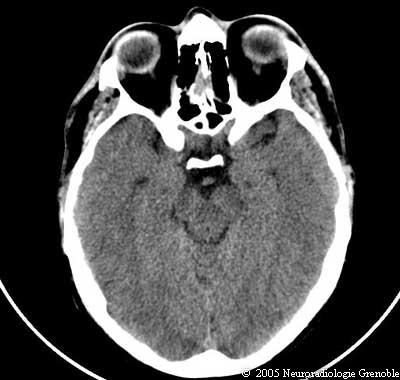

Radioanatomie TDM de l'encéphale

TDM cérébrale sans injection